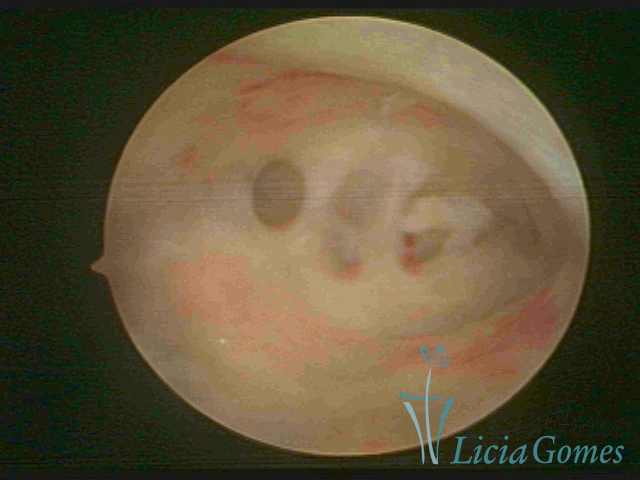

SINÉQUIA TIPO MUCOSA